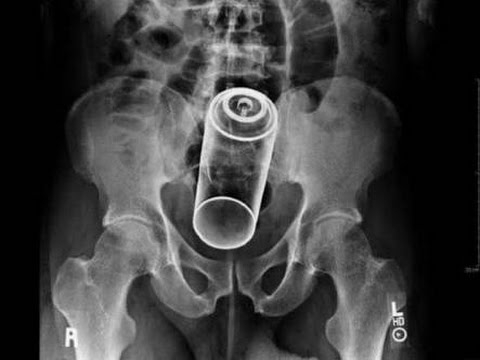

O Şişe Oraya Bakın Nasıl Girmiş

20 Mart 2022 Pazar 23:09Röntgen filmlerinden çıkan akıl almaz şeyler

Hastane koridorlarına düşenler bilir… Doktora görün, tahlilleri yaptır, röntgenleri çektir falan filan derken insanın ömründen ömür gider. Gelin görün ki bu sefer çektirilen röntgenlerde öyle ilginç şeyler çıkmış ki ağzımız açık kaldı…